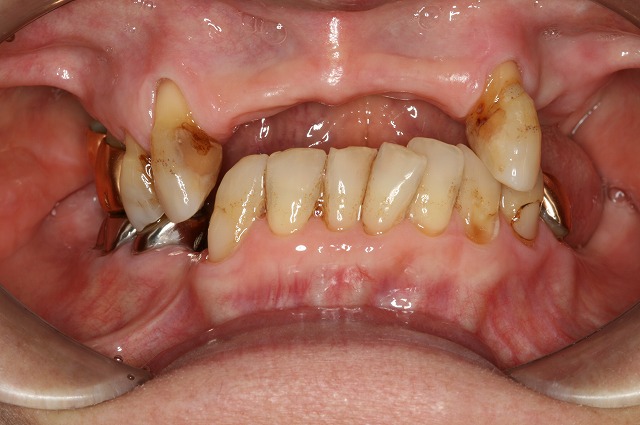

CASE02

Before

After

| 主訴 |

物が全く噛めないからなんとかしてほしい。

長年の入れ歯生活で噛めないから噛むところを探して歯が倒れ込んでどこで噛んだらいいかもわからない状態だった。 |

| 施術内容 |

インプラント…下顎4本 /

サイナスリフト…1部位 /

ソケットリフト…1部位 /

インプラントオーバーデンチャー(インプラント)…2本/

片顎部分矯正 |

| 治療期間 |

2年(35回) |